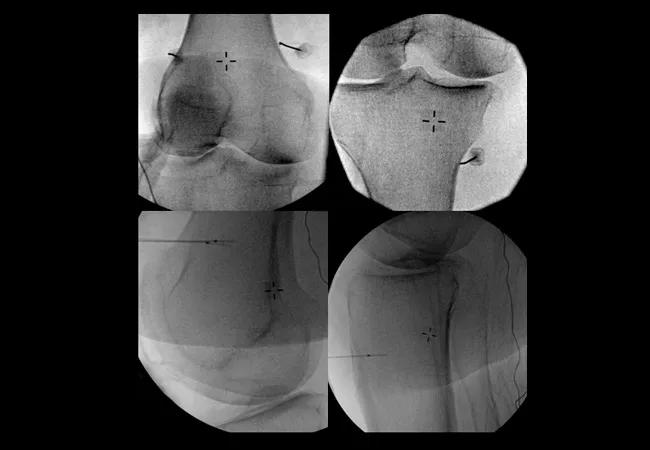

Genicular nerve blocks can be performed under fluoroscopic or ultrasound guidance. Nerves are targeted adjacent to the periosteum on the medial aspect of the tibia, and at both the medial and lateral aspects of the femur at the junctions of the shaft and the epicondyle.

Under fluoroscopic guidance, we approach the target by introducing a spinal needle from either an anteroposterior or lateral entry point with the final position residing adjacent to the bone. After negative aspiration, some physicians elect to administer contrast to exclude vascular uptake, avoiding a false negative result. To conclude the procedure, 2 mL of local anesthetic is deposited on each of the superolateral, superomedial and inferomedial genicular nerves.